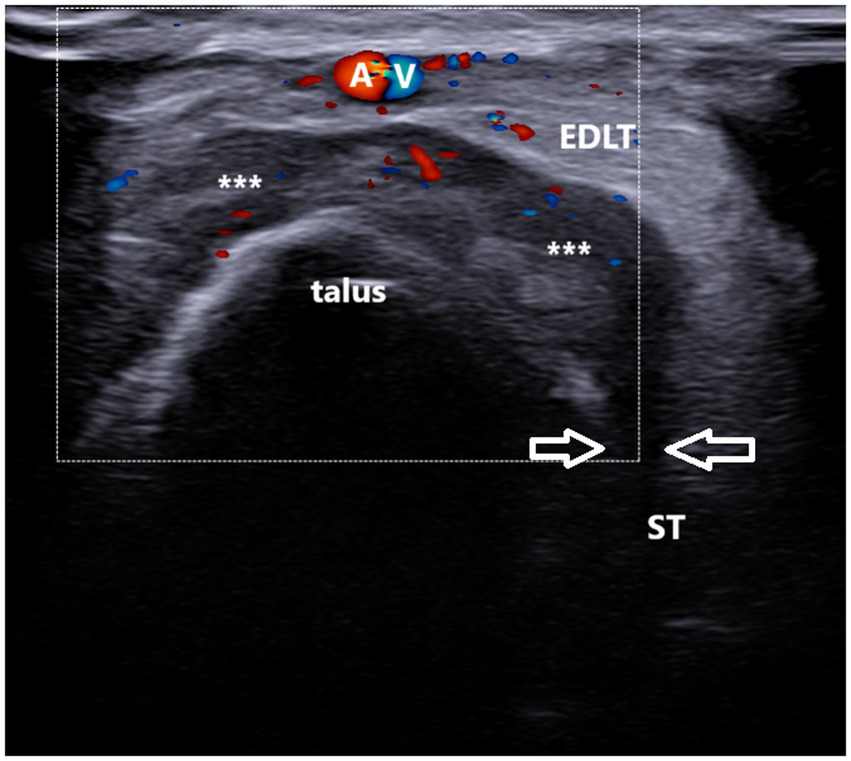

Figure 5

A 37-year-old patient with gout. Ultrasound image showing unilocular, power Doppler-positive GB with the transducer positioned in the short axis of the foot (left side is medial). The transverse ultrasound image of the dorsolateral ankle reveals a hypoechoic to heteroechoic unilocular fluid collection (***) between the extensor digitorum longus tendon (EDLT) and the talus, extending from the sinus tarsi (between arrows). ST, sinus tarsi; A and V, dorsalis pedis artery and vein; and EDLT, extensor digitorum longus tendon.

In the longitudinal plane, the GB had an ellipsoid shape and was located between the EDL tendon and the talus (Figure 4). Its middle portion was the thickest, while the inferior and superior poles narrowed sharply. We did not notice synovial hypertrophy in any recorded bursae. PD signals were registered in only four cases (Figure 5, Supplementary Video 2). Due to the small number of the PD-positive bursitis cases, the exact pattern (i.e., internal or along the bursal wall) and grade of the signal were not analyzed separately.